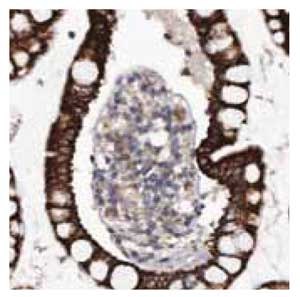

Anti-MGLL.Product No. HPA011994: Immunohistochemical staining of human small intestine shows strong cytoplasmic positivity in glandular cells.